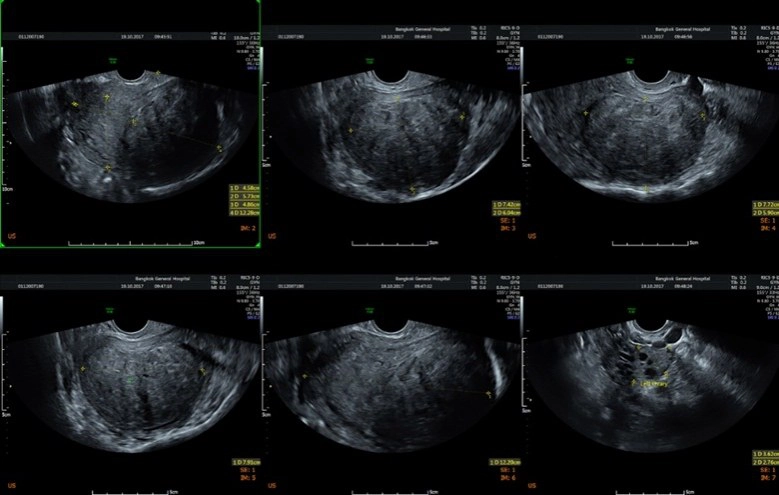

อันดับสอง"โรคซีสต์รังไข่"รังไข่เป็นอวัยวะขนาดเล็กที่อยู่บริเวณด้านข้างปีกมดลูกทั้ง 2 ข้าง ทำหน้าที่ในการสร้างฮอร์โมนต่างๆ ของผู้หญิงให้สมดุล ในทุกๆ เดือนรังไข่จะผลิตไข่ใบเล็กๆ ออกมา โดยไข่จะเคลื่อนจากด้านล่างผ่านท่อนำไข่ เพื่อเตรียมพร้อมผสมกับอสุจิของเพศชาย ส่วนซีสต์มีลักษณะเป็นถุงที่เต็มไปด้วยของเหลวที่สามารถก่อตัวขึ้นได้ในรังไข่ เมื่อเกิดการตกไข่ผิดปกติ จึงทำให้เกิดการคั่งของถุงน้ำในรังไข่ เกิดไข่ไม่ตก เกิดเป็นถุงน้ำขนาดเล็กในรังไข่มีการแบ่งเซลล์ที่ผิดปกติ"ซีสต์ในรังไข่"หลักๆ มี2ชนิด คือ ซีสต์ที่สามารถหายเองได้ กับซีสต์ที่ไม่สามารถหายได้เอง ซึ่งซีสต์ที่หายเองได้ คือซีสต์ที่เกิดขึ้นได้จากฮอร์โมนของผู้หญิงในทุกๆ รอบเดือน และเป็นซีสต์ที่พบได้บ่อยที่สุด ส่วนซีสต์ที่หายเองไม่ได้ และต้องได้รับการผ่าตัด เช่น ช็อกโกแลตซีสต์ เดอร์มอยด์ซีสต์ และอื่นๆ มีทั้งกลุ่มมะเร็ง และไม่ใช่มะเร็ง เป็นต้น

ซีสต์ในรังไข่ที่น่ากลัวคือ"มะเร็ง"เพราะไม่สามารถวินิจฉัยด้วยเพียงแค่การตรวจอัลตร้าซาวด์(ultrasound) การยืนยันการวินิจฉัยโรคเพื่อให้ได้ข้อเท็จจริง คือต้องตัดชิ้นเนื้อไปตรวจด้วยวิธีการผ่าตัดส่องกล้องเท่านั้น สำหรับ"ช็อกโกแลตซีสต์"เป็นซีสต์ที่มีอาการ เช่น ปวดท้องช่วงมีประจำเดือนแบบมากกว่าปกติ ส่วนซีสต์อื่นๆ มักไม่มีอาการ โดยเฉพาะ"มะเร็ง" 80%มักไม่มีอาการ แต่คนไข้มักจะมาพบแพทย์ด้วยอาการท้องบวมอย่างเห็นได้ชัด ท้องอืด แน่นท้อง น้ำหนักไม่ค่อยลง สำหรับอาการปวดท้องน้อยเฉียบพลันนั้น อาจเกิดจากซีสต์รั่วหรือบีบขั้ว ทำให้เกิดอาการปวด บางคนโชคร้ายซีสต์ที่เป็นมะเร็งแตก ส่งผลให้มะเร็งแพร่กระจายลามไปทั่วอวัยวะอื่นๆ ต้องตัดรังไข่ออก หลังผ่าตัดต้องรับการบำบัดด้วยคีโมต่อ

หรือบางคนเป็น"ซีสต์แบบบีบขั้ว"ก็ต้องตัดรังไข่ออกเช่นกัน เพราะเนื้อตายเนื่องจากเลือดไปเลี้ยงไม่ได้ บางคนไม่อยากมีลูกแล้วและไม่อยากกลับมาเป็นซีสต์อีกก็ตัดรังไข่ออก หรือเข้าสู่วัยทองแล้วก็สามารถตัดออกได้ กรณีคนที่ตัดแต่ซีสต์ออก แต่ไม่ได้เอารังไข่ออกก็มีโอกาสกลับมาเป็นซีสต์ได้อีก ซึ่งการรักษาสามารถส่องกล้องผ่าตัดได้เหมือนการรักษาเนื้องอกในมดลูก